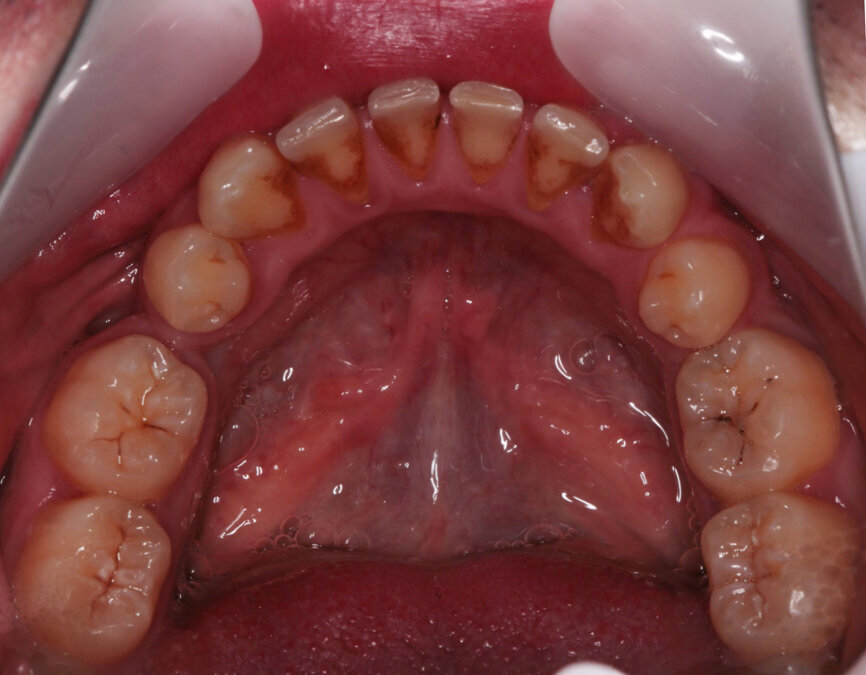

Fig. 5: Pre-treatment upper occlusal view

Fig. 6: Pre-treatment lower occlusal view